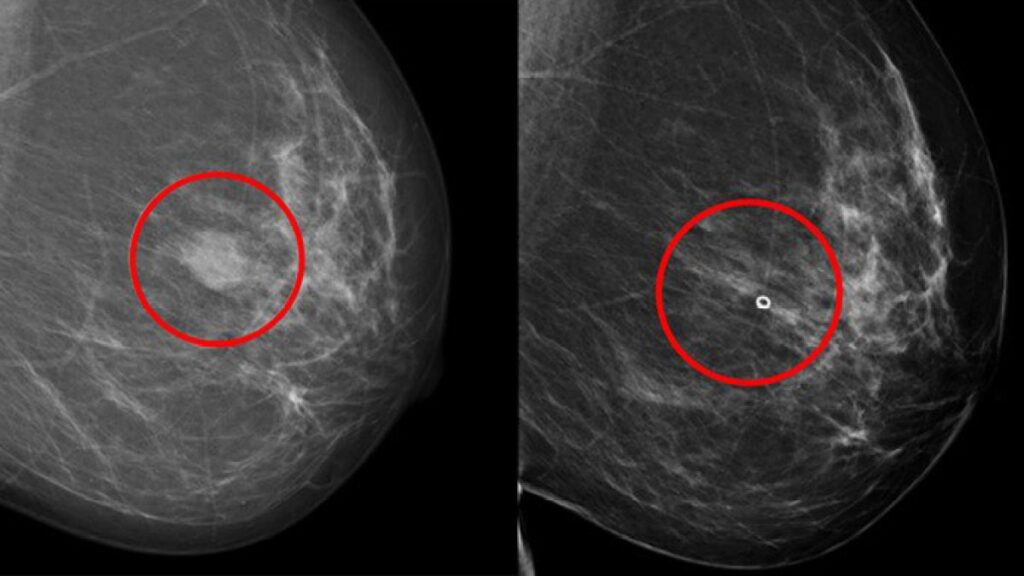

El método que han desarrollado los investigadores del Karolinska se basa en aislar y cultivar no solo células tumorales, sino también las llamadas células de soporte de pacientes con cáncer de mama.

El estudio actual demuestra que es posible establecer este tipo de modelos tumorales celulares a partir de tumores de mama y que son similares a los tumores de origen de las pacientes en aspectos relevantes, por ejemplo genéticamente y en cuanto a diferentes marcadores proteicos.

Los modelos tumorales se crearon a partir de biopsias de 98 pacientes operadas de cáncer de mama, y en ellos se probaron más de 35 fármacos contra el cáncer de mama existentes y en fase de desarrollo.

Los investigadores pudieron comprobar que la sensibilidad a los fármacos que mostraban los modelos tumorales coincidía en gran medida con los conocimientos actuales sobre las opciones de tratamiento basadas en los tipos de tumores de pacientes y que, en algunos casos, los modelos eran sensibles a los fármacos que estaban en fase de desarrollo.

A partir de biopsias tomadas antes de la cirugía, los investigadores crearon modelos tumorales para cada paciente y los expusieron a los mismos fármacos que recibió la paciente.

Los resultados muestran que las respuestas al tratamiento predichas por el modelo tumoral coincidieron en líneas generales con las respuestas al tratamiento que la paciente mostró posteriormente.

Por ejemplo, el modelo predijo la respuesta al tratamiento del fármaco quimioterapéutico epirubicina con una precisión del 90 por ciento, mientras que cuatro de las cuatro pacientes tratadas y sometidas a pruebas con fármacos de anticuerpos monoclonales anti-HER2 mostraron coherencia.